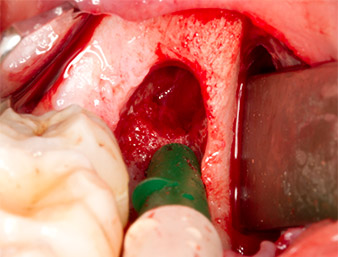

Tras una anestesia local y por conducción, el campo quirúrgico se abrió mediante los tejidos blandos para tener un acceso bucal-retromolar y se dejó expuesto (figura 3).

El tejido situado por encima del resto radicular no se había osificado por completo y constaba en su mayor parte de un tejido granulado con alteraciones inflamatorias (figura 4).